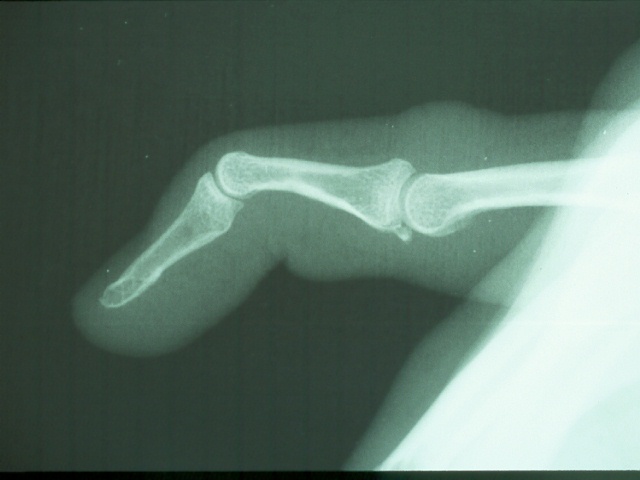

Clinical Example: Mallet fingers

mallet finger